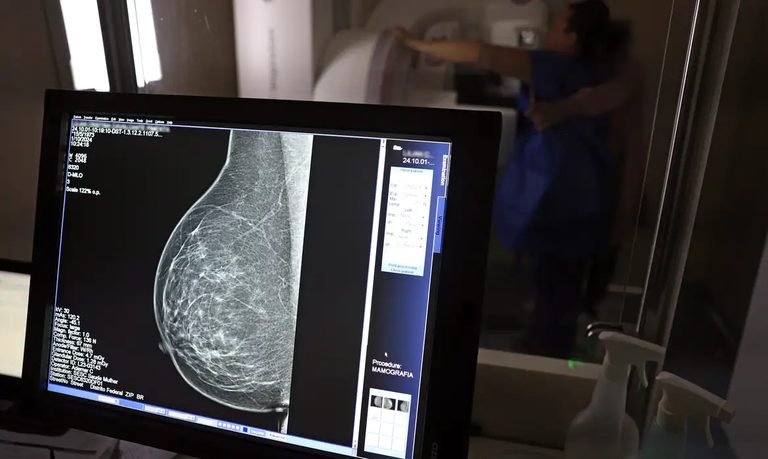

Foi publicada no Diário Oficial da União desta sexta-feira, 19 de dezembro, a Lei nº 15.284 , que fortalece o acesso das mulheres ao exame de mamografia fornecido pelo Sistema Único de Saúde (SUS). A partir de agora, o procedimento é garantido a mulheres a partir dos 40 anos de idade. Anteriormente, a idade em que o atendimento era oferecido, salvo casos especiais, era 50 anos.

AMPLA COBERTURA — Em 2024, o Sistema Único de Saúde (SUS) realizou aproximadamente 4 milhões de mamografias para rastreamento e 376,7 mil exames diagnósticos. Esses números refletem a manutenção de uma ampla cobertura no país, reforçando a importância do rastreamento e do diagnóstico precoce para salvar vidas e garantir mais qualidade na atenção à saúde das mulheres.